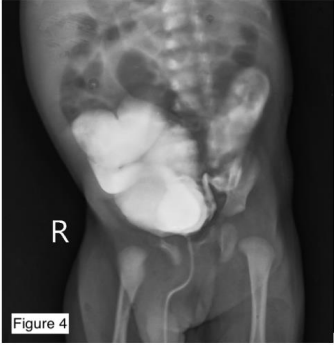

Figure 4: A Micturating Urethrogram - Lateral view - showing bilateral grossly dilated ureter and renal pelvis along with posterior urethral valve as a narrowing in the posterior urethra.

Posterior urethral valves (P.U.V.s), also referred to as congenital obstructing posterior urethral membranes (C.O.P.U.M.) is a congenital malformation affecting males where the membranous folds of the urogenital membrane obstruct the membranous and prostatic urethra. It is a congenital disorder only seen in males, with an incidence of 1 per 4000 to 1 per 25000 live births in some areas. Type 1 P.U.V. results from the abnormal insertion and absorption of the distal Wolffian duct during the development of the bladder. Type 3 PUV is observed as a membrane in the posterior urethra, originating from the incomplete canalisation between the anterior and the posterior urethra. Type 2 P.U.V. is now considered a normal anatomical variant. Regardless of the type, P.U.V.s present with urinary tract obstruction, bladder distension, abdominal distension, difficulty voiding, poor stream of urine, recurrent Urinary Tract Infection (U.T.I.), diurnal enuresis and a failure to thrive. They are diagnosed Antenatally by Ultrasonography showing distended or thick-walled bladder, bilateral hydroureters, and bilateral hydronephrosis. However, the gold standard for the diagnosis is a Micturating CystoUrethrogram (MCU), also known as a Voiding Cystourethrogram (V.C.U.) shows dilation/elongation of the posterior urethra during voiding along with signs of vesicoureteral reflux if present. This patient was antenatally diagnosed with posterior urethral valves at seven months of fetal age and came to us for further management. Antenatal diagnosis of Posterior Urethral Valves on Ultrasonogram involves visualisation of 1. Keyhole sign- due to the distension of the urethral proximal to the valves and a distended bladder, 2. marked distention or hypertrophy of the bladder, 3. Hydronephrosis and hydroureter. An Ultrasonogram of the abdomen and pelvis done postnatally revealed bilateral gross hydroureteronephrosis, which was missed on antenatal scans. The baby was born to a G2P1L1 mother and weighed 3.04kg at birth. The baby cried immediately after birth and maintained oxygen saturation at 100% on room air. The patient was managed with Cystoscopy with Posterior Urethral Valve fulguration with circumcision.